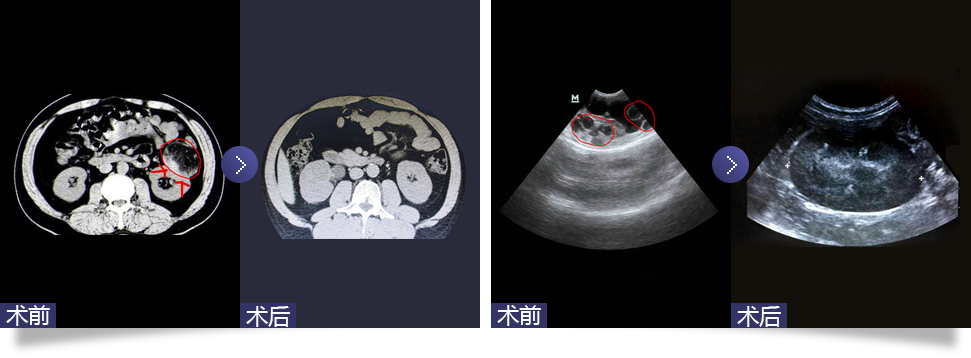

腹腔鏡下腎囊腫去頂減壓術(shù)

Laparoscopic renal cyst deparization and decompression

隨著腹腔鏡技術(shù)在泌尿外科領(lǐng)域的廣泛應(yīng)用,腹腔鏡下囊腫去頂減壓術(shù)成為治療腎囊腫的主要方法。通過腹腔鏡下用超聲刀切開腹膜,傷口為1.5-2.0cm,分離腎周脂肪,找到充分暴露的腎囊腫壁邊緣,切開囊腫壁并吸凈囊液。